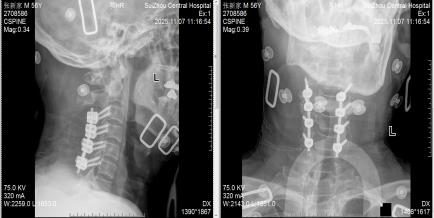

圖3:術(shù)后X線見內(nèi)固定位置良好

3.治療原則:一旦確診,72小時(shí)內(nèi)是手術(shù)黃金期,核心是清除血腫、解除神經(jīng)壓迫。隨州市中心醫(yī)院采用的急診減壓手術(shù),能最大程度挽救神經(jīng)功能,這也是5例患者均無后遺癥的關(guān)鍵;